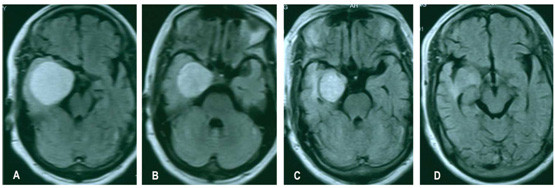

老年颅内良性肿瘤:当患者不能耐受开颅手术时,肿瘤对放射外科治疗相对敏感时,射波刀低分割治疗颅内良性肿瘤有明显优势。将治疗肿瘤的剂量分割成3-5次,可以提高控制肿瘤的剂量,同时减轻副反应。如图6,患者74岁,右侧海绵窦海绵状血管瘤,肿瘤大,不能耐受开颅手术,实施周边剂量21Gy,分割成3次照射,治疗后3个月肿瘤缩小,患者的头痛症状减轻,治疗后14个月,肿瘤进一步缩小。图7为75岁的垂体瘤患者,肿瘤较大,但是患者有内科疾病不能耐受手术,实施周边剂量22.5Gy,分割3次治疗。尽管肿瘤紧贴视神经视交叉,射波刀治疗后,患者视力未受影响,治疗后8个月复查MRI显示肿瘤缩小。

图6:右侧海绵窦海绵状血管瘤(影像学诊断)射波刀治疗前后的比较。A: 射波刀治疗前MRI;B:射波刀治疗后3个月,复查MRI显示肿瘤明显缩小。C和D:治疗后14个月,肿瘤进一步缩小,患者无不适。

图7:高龄垂体瘤患者射波刀治疗前后增强MRI比较。A和B: 射波刀治疗前;C和D:射波刀治疗后8个月,肿瘤缩小,患者视力未受影响。